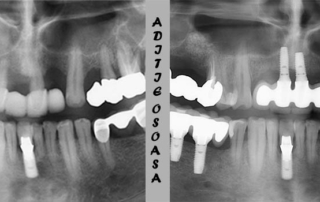

Dental bone addition

On the occasion of this article I want to address those of you who have been told at some point that you lacked sufficient bone for a dental implant to be applied in that region. In addition to dental extractions, there are several other reasons why you have lost significant bone volume. I shall mention some of them: Acute, aggressive infections of the tooth in question; Untreated chronic dental infections; Inadvertent and/or aggressive [...]